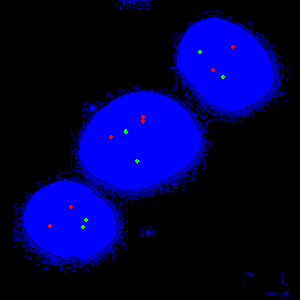

Figure 1

Close-up of a group of nuclei including gene probes.